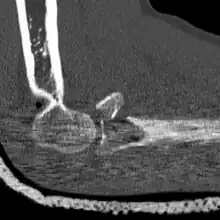

CT scan showing a radial head fracture -